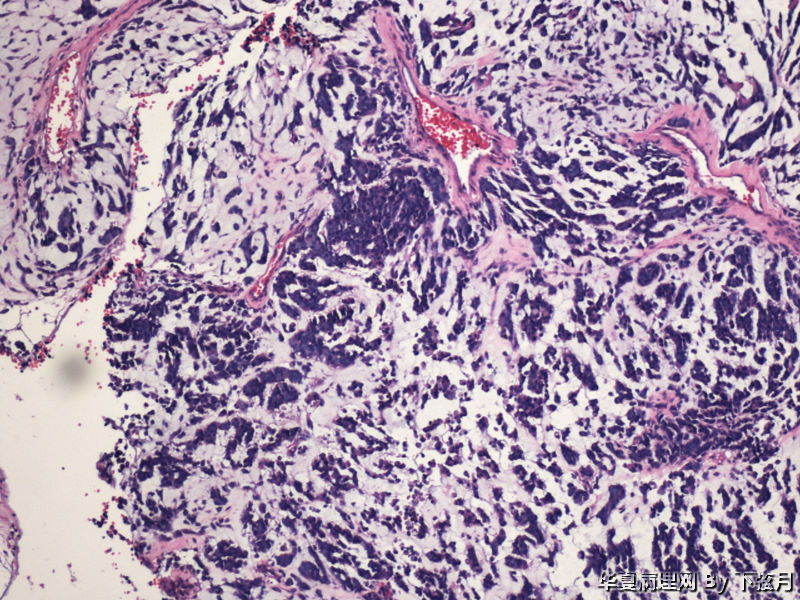

左侧颞叶及胼胝体膝部占位图1

名称:图1

描述:HE 40倍

从图1可见肿瘤似位于脑皮质外围,有粘液背景,部分如脊索瘤样,倾向于脊索瘤样脑膜瘤。